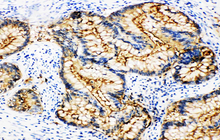

- Immunohistochemistry (IHC) technique

Histological methods includes sample processing in the pathology laboratory, preparation of the slide and its examination under a microscope, sample fixation, molding, microtome cutting, staining and assembly of the slides.